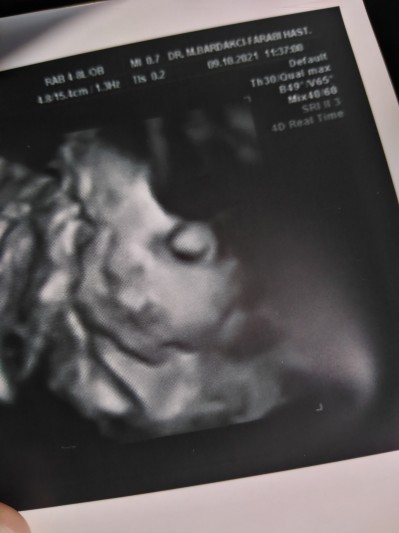

(391 puan)

Bu da 2 gün önce kızçemin fotografı. baş aşağı pozisyonda hala minnağım

image

(878 puan)

Maşallah ne tatlı minnak♥️ benim doktor beni kandırıyor kesin